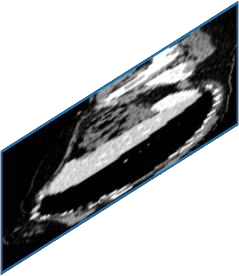

Due to the constraints of the imaging device and high cost in operation time, computer tomography (CT) scans are usually acquired with low intra-slice resolution. Improving the intra-slice resolution is beneficial to the disease diagnosis for both human experts and computer-aided systems. To this end, this paper builds a novel medical slice synthesis to increase the between-slice resolution. Considering that the ground-truth intermediate medical slices are always absent in clinical practice, we introduce the incremental cross-view mutual distillation strategy to accomplish this task in the self-supervised learning manner. Specifically, we model this problem from three different views: slice-wise interpolation from axial view and pixel-wise interpolation from coronal and sagittal views. Under this circumstance, the models learned from different views can distill valuable knowledge to guide the learning processes of each other. We can repeat this process to make the models synthesize intermediate slice data with increasing inter-slice resolution. To demonstrate the effectiveness of the proposed approach, we conduct comprehensive experiments on a large-scale CT dataset. Quantitative and qualitative comparison results show that our method outperforms state-of-the-art algorithms by clear margins.